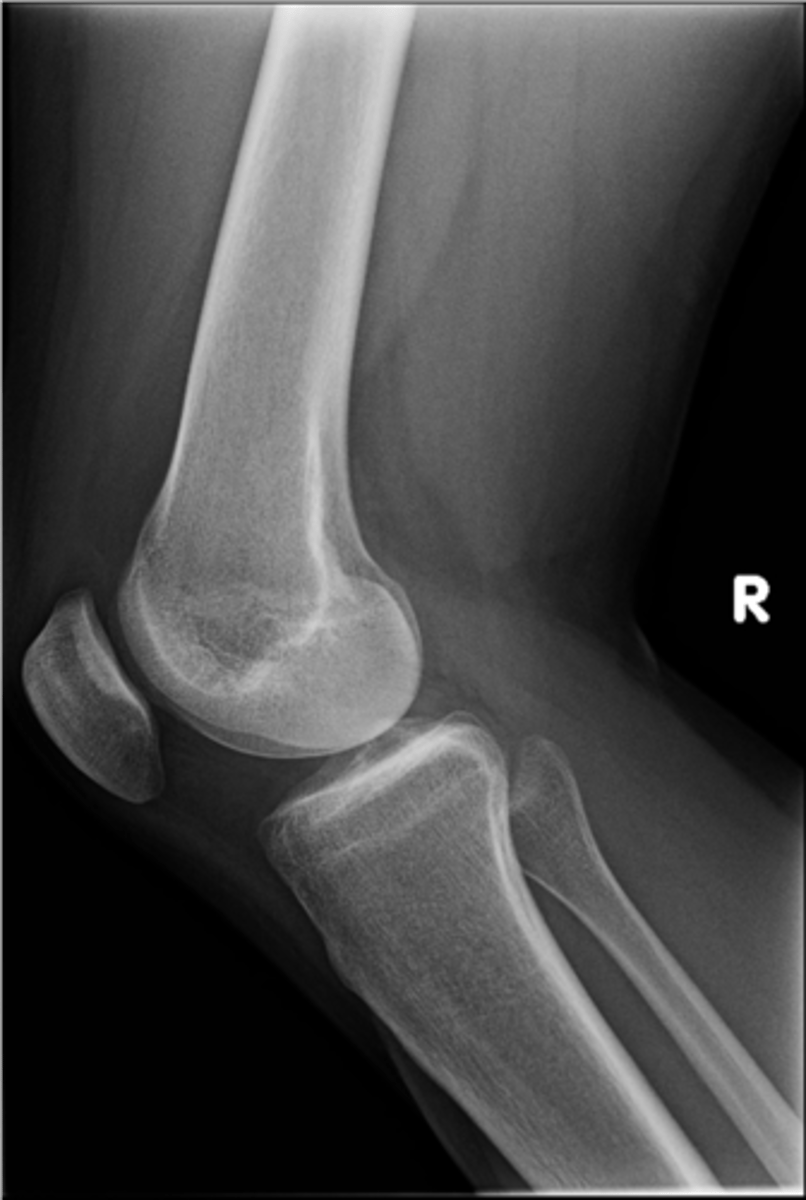

Lateral knee

ID standard knee projection

<p>ID standard knee projection</p>

Flexion

Lateral knee projections are generally taken with _____

<p>Lateral knee projections are generally taken with _____</p>

Infrapatellar pouch

ID 29

<p>ID 29</p>

Hoffa's fat pad

Another term for infrapatellar pouch

<p>Another term for infrapatellar pouch</p>

Quadriceps tendon

ID 30

<p>ID 30</p>

Prefemoral fat pad

ID 31

<p>ID 31</p>

Suprapatellar pouch

ID 32

<p>ID 32</p>

Ludloff's patch/spot

- Not a true anatomical structure

- Appears due to less bone being traversed anteriorly than posteriorly